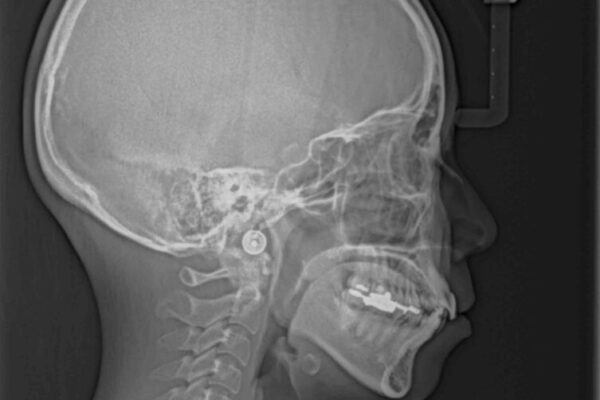

前歯のデコボコと上顎の前突感による口の閉じにくさを気にして来院された患者様です。

目立たない装置を希望されたので、上顎が裏側装置のハーフリンガルを選択し、上下左右の小臼歯(計4歯)を抜歯して矯正治療を行うこととしました。

治療途中

• デコボコと口元の突出感 ハーフリンガルでの抜歯矯正 治療途中画像